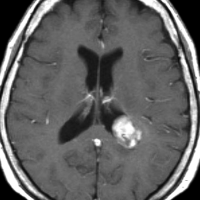

神経線維腫症1型に合併した退形成を示す anaplastic PXA

もともと停止性水頭症があり経過観察を受けていたNF-1の患者さんに発生したものです。嘔気と左片麻痺で発症しました。 開頭手術で亜全摘出(ほぼ全摘)しました。

術後に小さな腫瘍が残っていた(左の画像)ので54Gy/27frの放射線治療をしましたが,無効でした。結局,再開頭手術で残存腫瘍を摘出しました。3年後に同じ部位で再発(中央の画像)したので,また開頭手術で摘出しました。そのまた3年後に同じ部位で再発しました(右側の画像)。この様に,摘出しきれなければ治らないし,摘出できれば治る可能性の高い腫瘍です。腫瘍床での再発は多いものの,転移とか脳深部への浸潤性増殖は少ないといえる腫瘍です。放射線治療が効きにくいということを併せて,atypical meningioma WHO grade 2と似た性格を有しています。